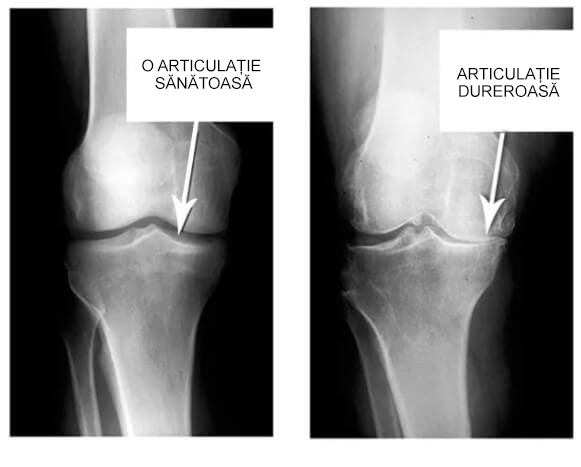

Uitați-vă la aceste imagini, puteți vedea că în imaginea din dreapta nu există un spațiu articular, oasele se freacă una de alta, provocând multă durere. Iar acest proces este foarte greu de oprit!

Cât timp credeți că este nevoie pentru ca țesuturile să se degradeze și articulația să se uzeze?".